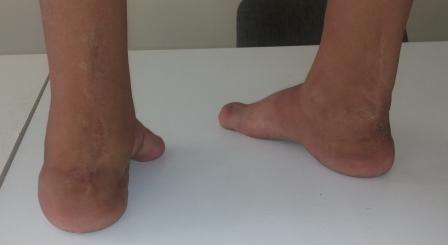

Уважаемые коллеги, специалисты подиатрии! Сегодня обратилась девочка

2004 г.р. , лет 7-8 назад оперирована в одной центральной клинике,

по-видимому, по поводу косолапости, ахиллопластика и аппаратом

Илизарова( документов нет).

Просит исправить деформацию и чтобы могла одеть нормальную обувь .Фото и

Р-графия предлагается, где имеется вывих в плюснефаланговом суставе и

медиальная девиация всех пальцев, 1- палец пассивно поднимается до

горизонтали, при этом подошвенная фасция сильно натягивается, но

разгибания нет, медиальная девиация пальцев исправлению поддается без труда.